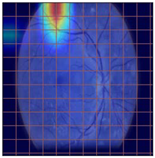

3.2. Models Explainability on the Test Set

| Original Image | VGG16 | ResNet-18 | DenseNet-121 |

|---|---|---|---|

![]() | ![]() | ![]() | ![]() |

| (a) | |||

| (b) | |||

| (c) | |||

| (d) | |||

| Model | Conformity with Normal Retinal Photos | Conformity with Abnormal Retinal Photos | Average Conformity |

| VGG16 | 0.2000 | 0.2414 | 0.2207 |

| ResNet-18 | 0.0294 | 0.0645 | 0.0469 |

| DenseNet-121 | 0.0385 | 0.0286 | 0.0336 |